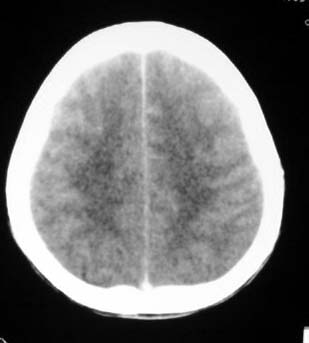

平片呢?如果有个平片让大家看看 学习下

平扫请阅ct7266,病人下午增强,所以只能分两次发.给大家带来的不便,请多多包涵.